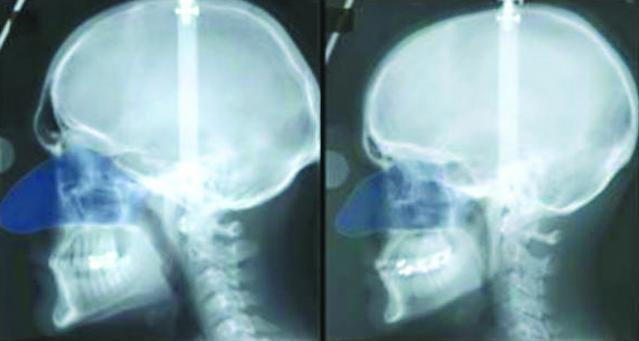

在現實生活中,有沒有發現男人的鼻子比女人大10%?美國艾奧瓦大學研究終於解開這個謎題,因為男人肌肉比例較多,比女性需要吸入更多氧氣。

研究員指,男女在出世直至11歲時,鼻子的大小相若,但到11歲後,男性鼻子就不成比例地增大。研究員解釋,男性在青春期開始後,有約95%體重來自非脂肪重量,他們的肌肉量逐漸增加,於是需要吸入更多氧氣讓肌肉增長;而女性的脂肪比例亦在青春期開始後增長。

研究又指,史前人類的鼻子較現代人大,因為史前人類的肌肉較多,現代人需要的氧氣較少,導致人類外觀上有變化。